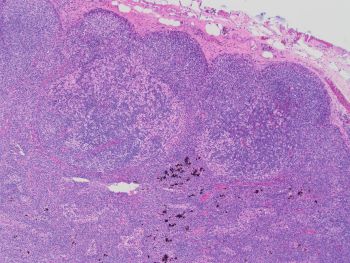

Images 1 and 2 show an enlarged lymph node with mostly intact architecture and marked paracortical expansion with pale staining areas. The expansion is mostly nodular. Although, areas of diffuse paracortical expansion are seen, such as on the left side of image 2. Images 3 and 4 show pale staining areas at high power magnification from different parts of the lymph node. Image 3 shows Langerhans and interdigitating dendritic cells with mostly small lymphocytes in the background. Image 4 shows Reed Sternberg cells with a mixed background of histiocytes, small lymphocytes, eosinophils, and plasma cells.